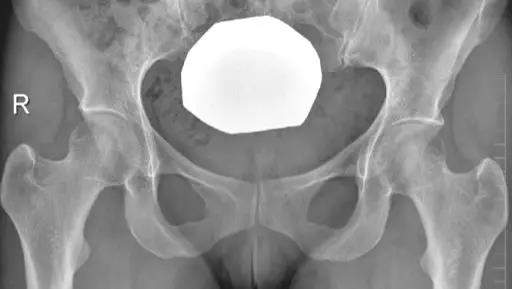

X线平片(首选方法):

- 骨盆正位片:尾骨尖端指向耻骨联合,且二者之间的距离是1~2 cm 。

- 能显示股骨近端、髋臼盂缘的骨性解剖异常。

- 正常髋关节X线表现。

- 中心边缘角(LCE角)正常范围为25一39;髋臼指数(AI)正常值>0;挤压指数(E/A+E)正常值<25%。

- IIL:髂坐线;AW:髋臼前壁缘;PW:髋臼后壁缘;A为股骨头被髋臼覆盖部分的宽度;E为股骨头未被髋臼覆盖部分的宽度;F为髋臼窝线。